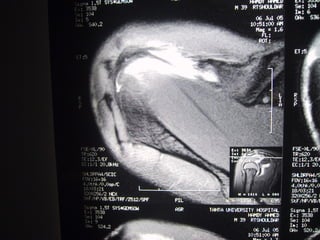

Case 6   Supraspinatus full thickness tear